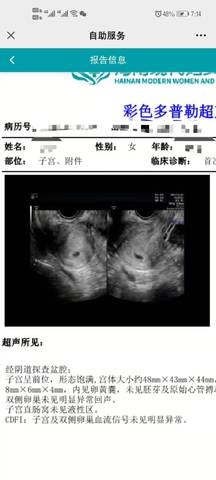

5周b超,帮忙看看是男还是女!!急急急!

journal_insert_pic_1686647304journal_insert_pic_1686647321

你好,根据你发的检查报告,是看不出宝宝的性别的,建议宝妈还是安心养胎,只要宝宝健康就好

看不出来,这个单上的数据是很难直接判断男孩还是女孩的哦,其实只要孩子健健康康就好,生下来才最准